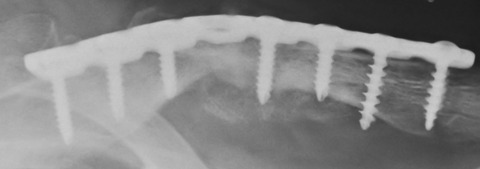

術後の単純X線像でも、偽関節部の全周性に移植骨が存在することを確認できます。ちょっとやり過ぎではと思うぐらいで充分だと思います。